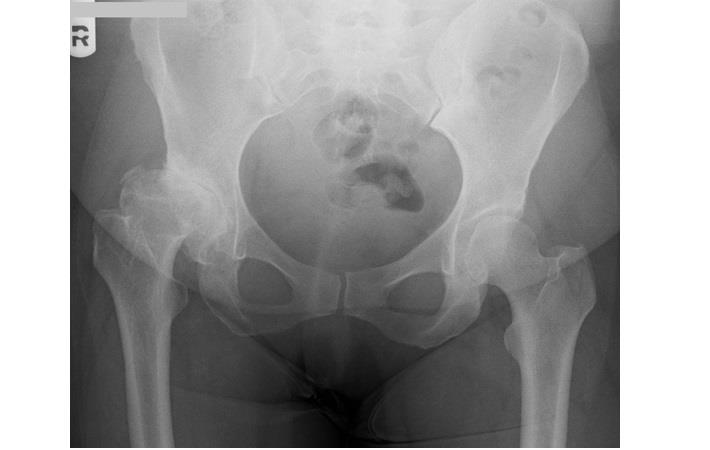

ניתוח החלפת מפרק ירך מתאים למטופלים הסובלים מכאבים ממושכים באזור המפרק שלא הוקלו למרות ביצוע של טיפולים שמרניים. ברוב המקרים, מדובר בכאב כרוני אליו נלוות תלונות כמו פגיעה בטווח התנועה והגבלה משמעותית בתפקוד. הסיבה השכיחה ביותר לפגיעה במפרק הירך היא שחיקת סחוסים. אולם, קיימים גם מצבים אחרים העלולים לגרום לפגיעה במפרק, כמו למשל מחלות דלקתיות כגון דלקת מפרקים שגרונית, מצבים לאחר חבלות ושברים, נמק של ראש הירך ואחרים.

בעבר היה נהוג לחשוש מניתוח החלפת מפרק עקב גיל צעיר או מבוגר מדי. כיום, כאשר נעשה שימוש בטכניקות מתקדמות יותר תוך בחירת סוג המשתל המתאים לכל מטופל וכאשר הניתוח מתאים מבחינה רפואית למצב המטופל – הגיל איננו מהווה מחסום, אך בהחלט מהווה גורם נוסף בסך השיקולים של המנתח.